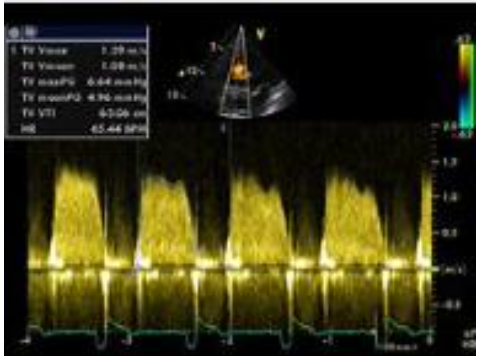

20

Q

Tricuspid Stenosis

Explain how to obtain mean PG

A

• Trace the peak waveform, start and finish at ) baseline

• the machine will calculate the mean PG

22

severity scale: P½t

severe?

≥190 m/s

23

severity scale: mean PG

≥ 5 mmHg

_Tricuspid Regurgitation_ murmur

a holosystolic murmur that increases with inspiration

26

_Tricuspid Regurgitation_ causes

* majority of normal patients (75%) have trace/mild TR * mosrt common cause of TR is secondary or functional TR due to: * annulr dilatation from RA/RV enlargement * associated with left heart disease * RV dysfunction * PH * myxomatous degeneration - most common cause of primary TR * Rheumatic TR - usually associated with TS * TV prolapse \*seen in 20% of cases with concominant MVP (**mid-to-late systolic or holosystolic)** * incomplete closure of TV due to: * pacemaker wire * tumor * RV infarct * pap muscle dysfunction * ruptured TV chordae * secondary TR due to frail leaflets (closed chest trauma, biopsy, vegetation) * carcinoid heart disease * congenital TR (Ebstein anomaly) * prosthetic valve disease

27

_Tricuspid Stenosis_ severity: inflow time-velocity integral

> 60cm